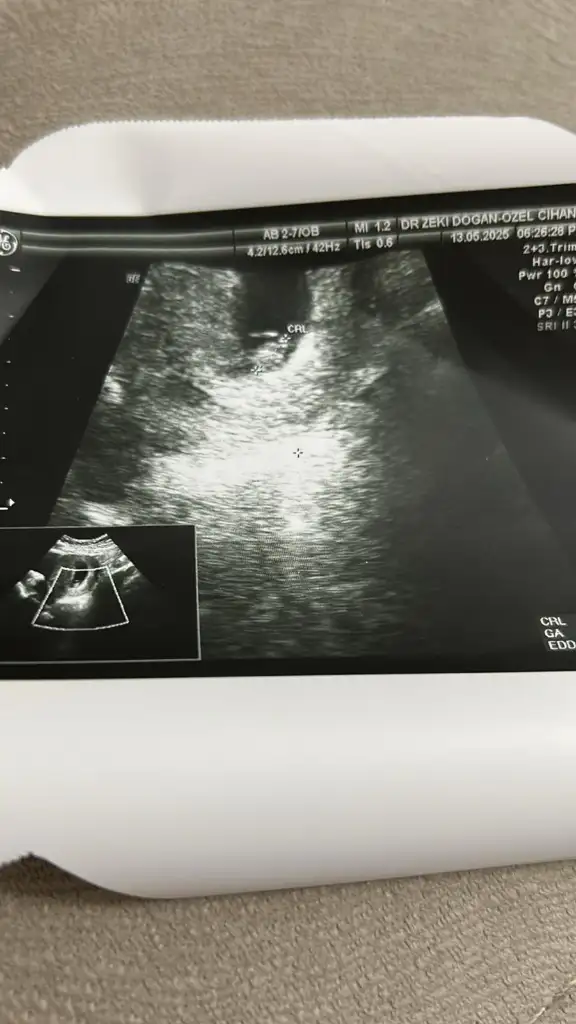

Banada bakar misini 6+1 karından ultrasonKızlar 6-8 haftalık ultrason görüntülerinizi atın tahmin yapalım . Ya da cinsiyeti öğrenen annelerimiz 6-8 haftalık görüntülerini atsın bize de fikir olsun

Bilemedim ama kız olabilirBanada bakar misini 6+1 karından ultrason